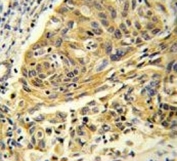

IHC staining of FFPE human lung cancer tissue with Clathrin heavy chain antibody. HIER: boil tissue sections in pH8 EDTA for 20 min and allow to cool before testing.